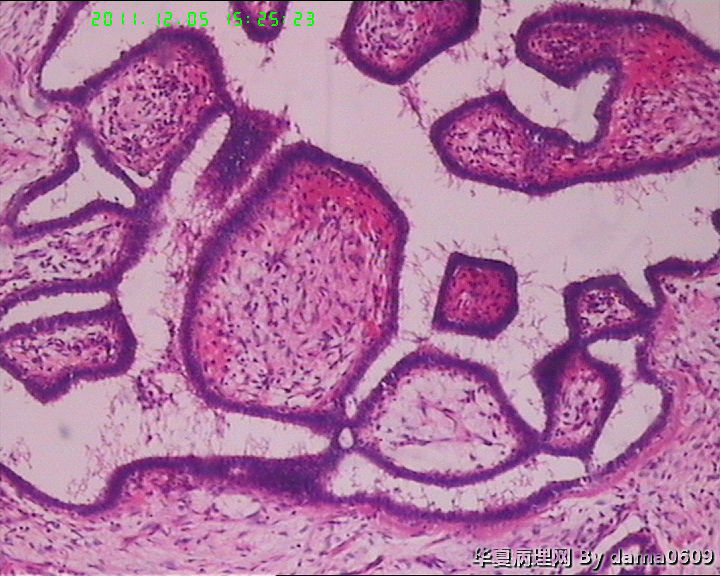

肿物一:镜下见乳腺小叶结构紊乱,小叶内、小叶间间质增生,构成肿瘤主质。增生间质呈梭形细胞样,细胞稀疏、异性不明显,其间见大量胶原纤维,小血管增生,局灶有红细胞渗出。见到一处导管大汗腺化生。

肿物二:镜下呈结节状,结节以导管或小叶为中心,围以增生的间质成分,梭形细胞构成,稀疏,增生的血管呈“鹿角状”。大结节内见局灶间质有出血或红细胞外渗,局灶导管内间质增生呈乳头/分叶状,上皮下无密集增生的间质细胞。结节大小不等,以窄带样纤维细胞束彼此分隔,互不融合,纤维细胞束细胞密集,内有增生的小血管。